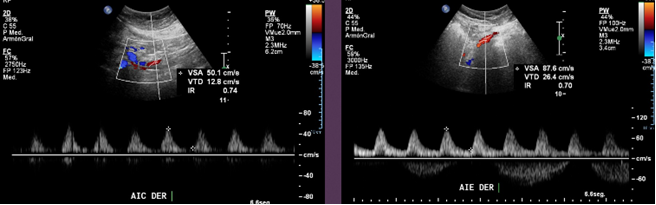

Se observan curvas monofásicas de baja resistencia con disminución de su velocidad en todas las ramas arteriales de ambas extremidades inferiores, tipo tardus parvus. Se evalúan arterias iliacas comunes y externas observando similares características.

Previo a la oclusión se observa curva pre oclusiva monofásica de baja velocidad.

Se observan curvas monofásicas de baja resistencia con pérdida de componente reverso diastólico y disminución de la velocidad sistólica en todo el árbol arterial de ambas extremidades inferiores. En la aorta abdominal distal, a 3 cm de la bifurcación, se observa un segmento oclusivo de la aorta con contenido ecogénico calcificado, sin flujo a este nivel. Previo a la oclusión se observa curva pre oclusiva monofásica de baja velocidad. Se observa flujo colateral paralelo a la oclusión que reconstituye el flujo en el origen de las arterias iliacas comunes, observándose flujos monofásicos hacia distal con reducción en aproximadamente un 60%